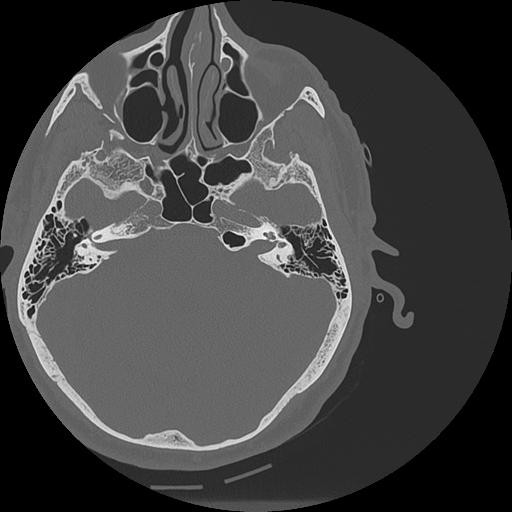

7 HUESO,,Vol,0.5,HUESO,,